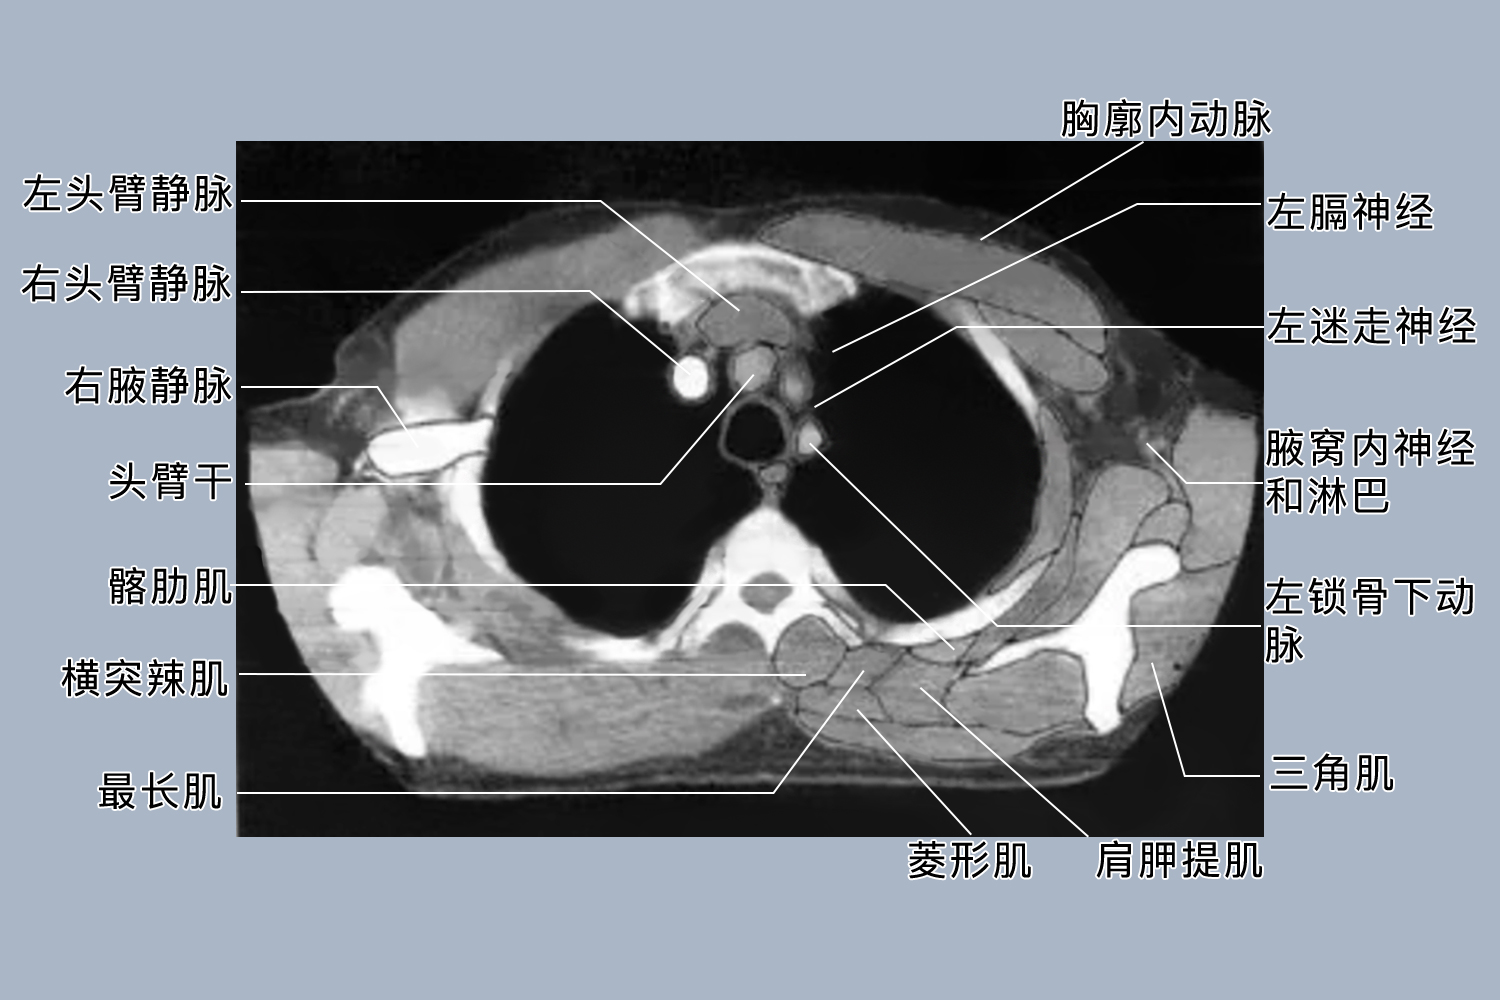

1、检查范围:胸部CT涵盖的范围更广,包括胸廓、胸骨、肋骨、胸椎、纵隔、心脏、大血管、气管、支气管、肺组织、胸膜、胸壁软组织等。而肺部CT主要集中在肺部,重点观察肺实质、肺间质、肺血管等结构。胸部CT检查范围广,能全面评估胸部的各种结构,肺部CT则更专注于肺部情况。